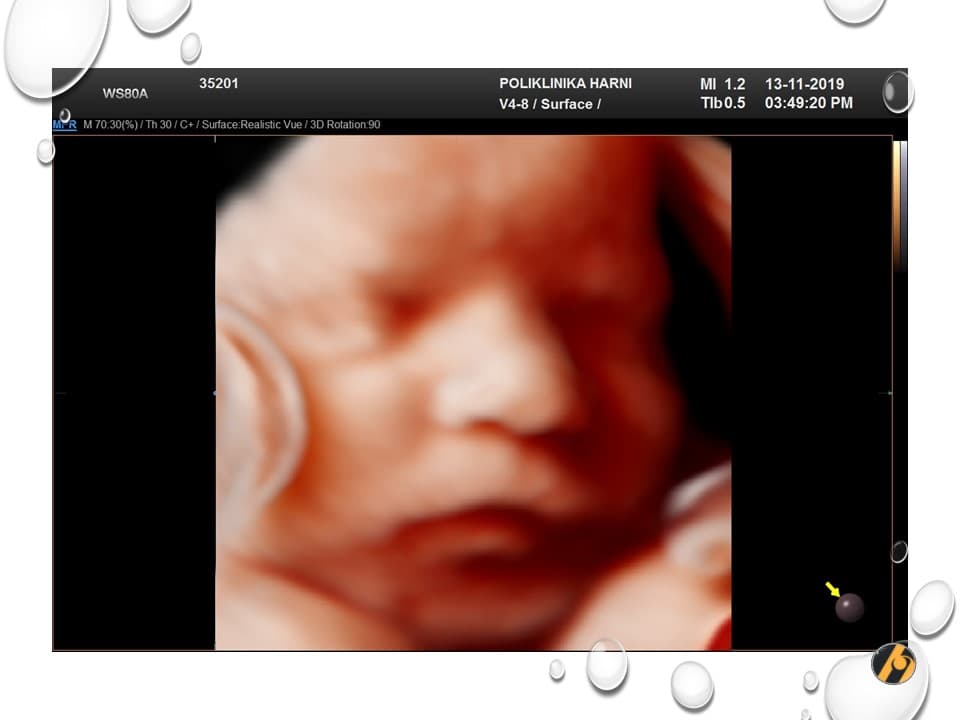

Vaša beba dugačka je oko 44 cm, a teška 2,300 – 2,550 g.

beba